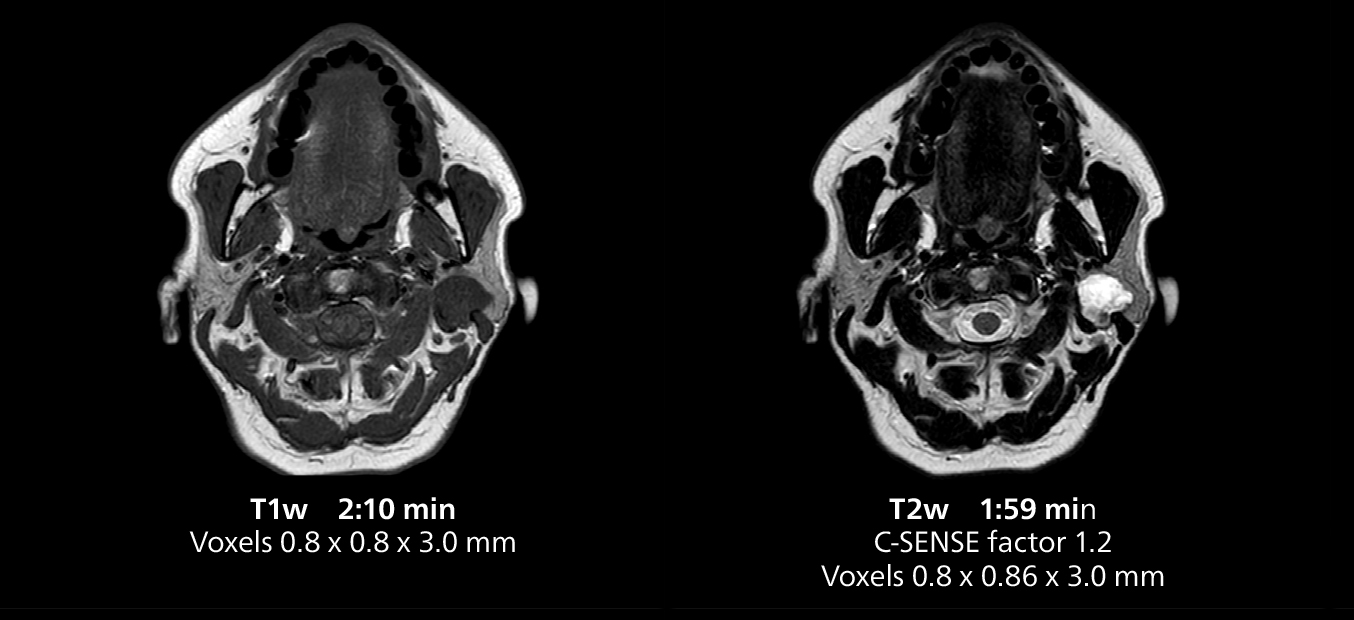

Salivary gland imaging on MR 5300

This MRI case illustrates imaging of salivary gland abnormalities with different sequences. Compressed SENSE allows to accelerate scanning while maintaining high quality. With mDIXON XD, different contrast types can be obtained from scanning one sequence.

Salivary gland imaging on MR 5300

This MRI case illustrates imaging of salivary gland abnormalities with different sequences. Compressed SENSE allows to accelerate scanning while maintaining high quality. With mDIXON XD, different contrast types can be obtained from scanning one sequence.